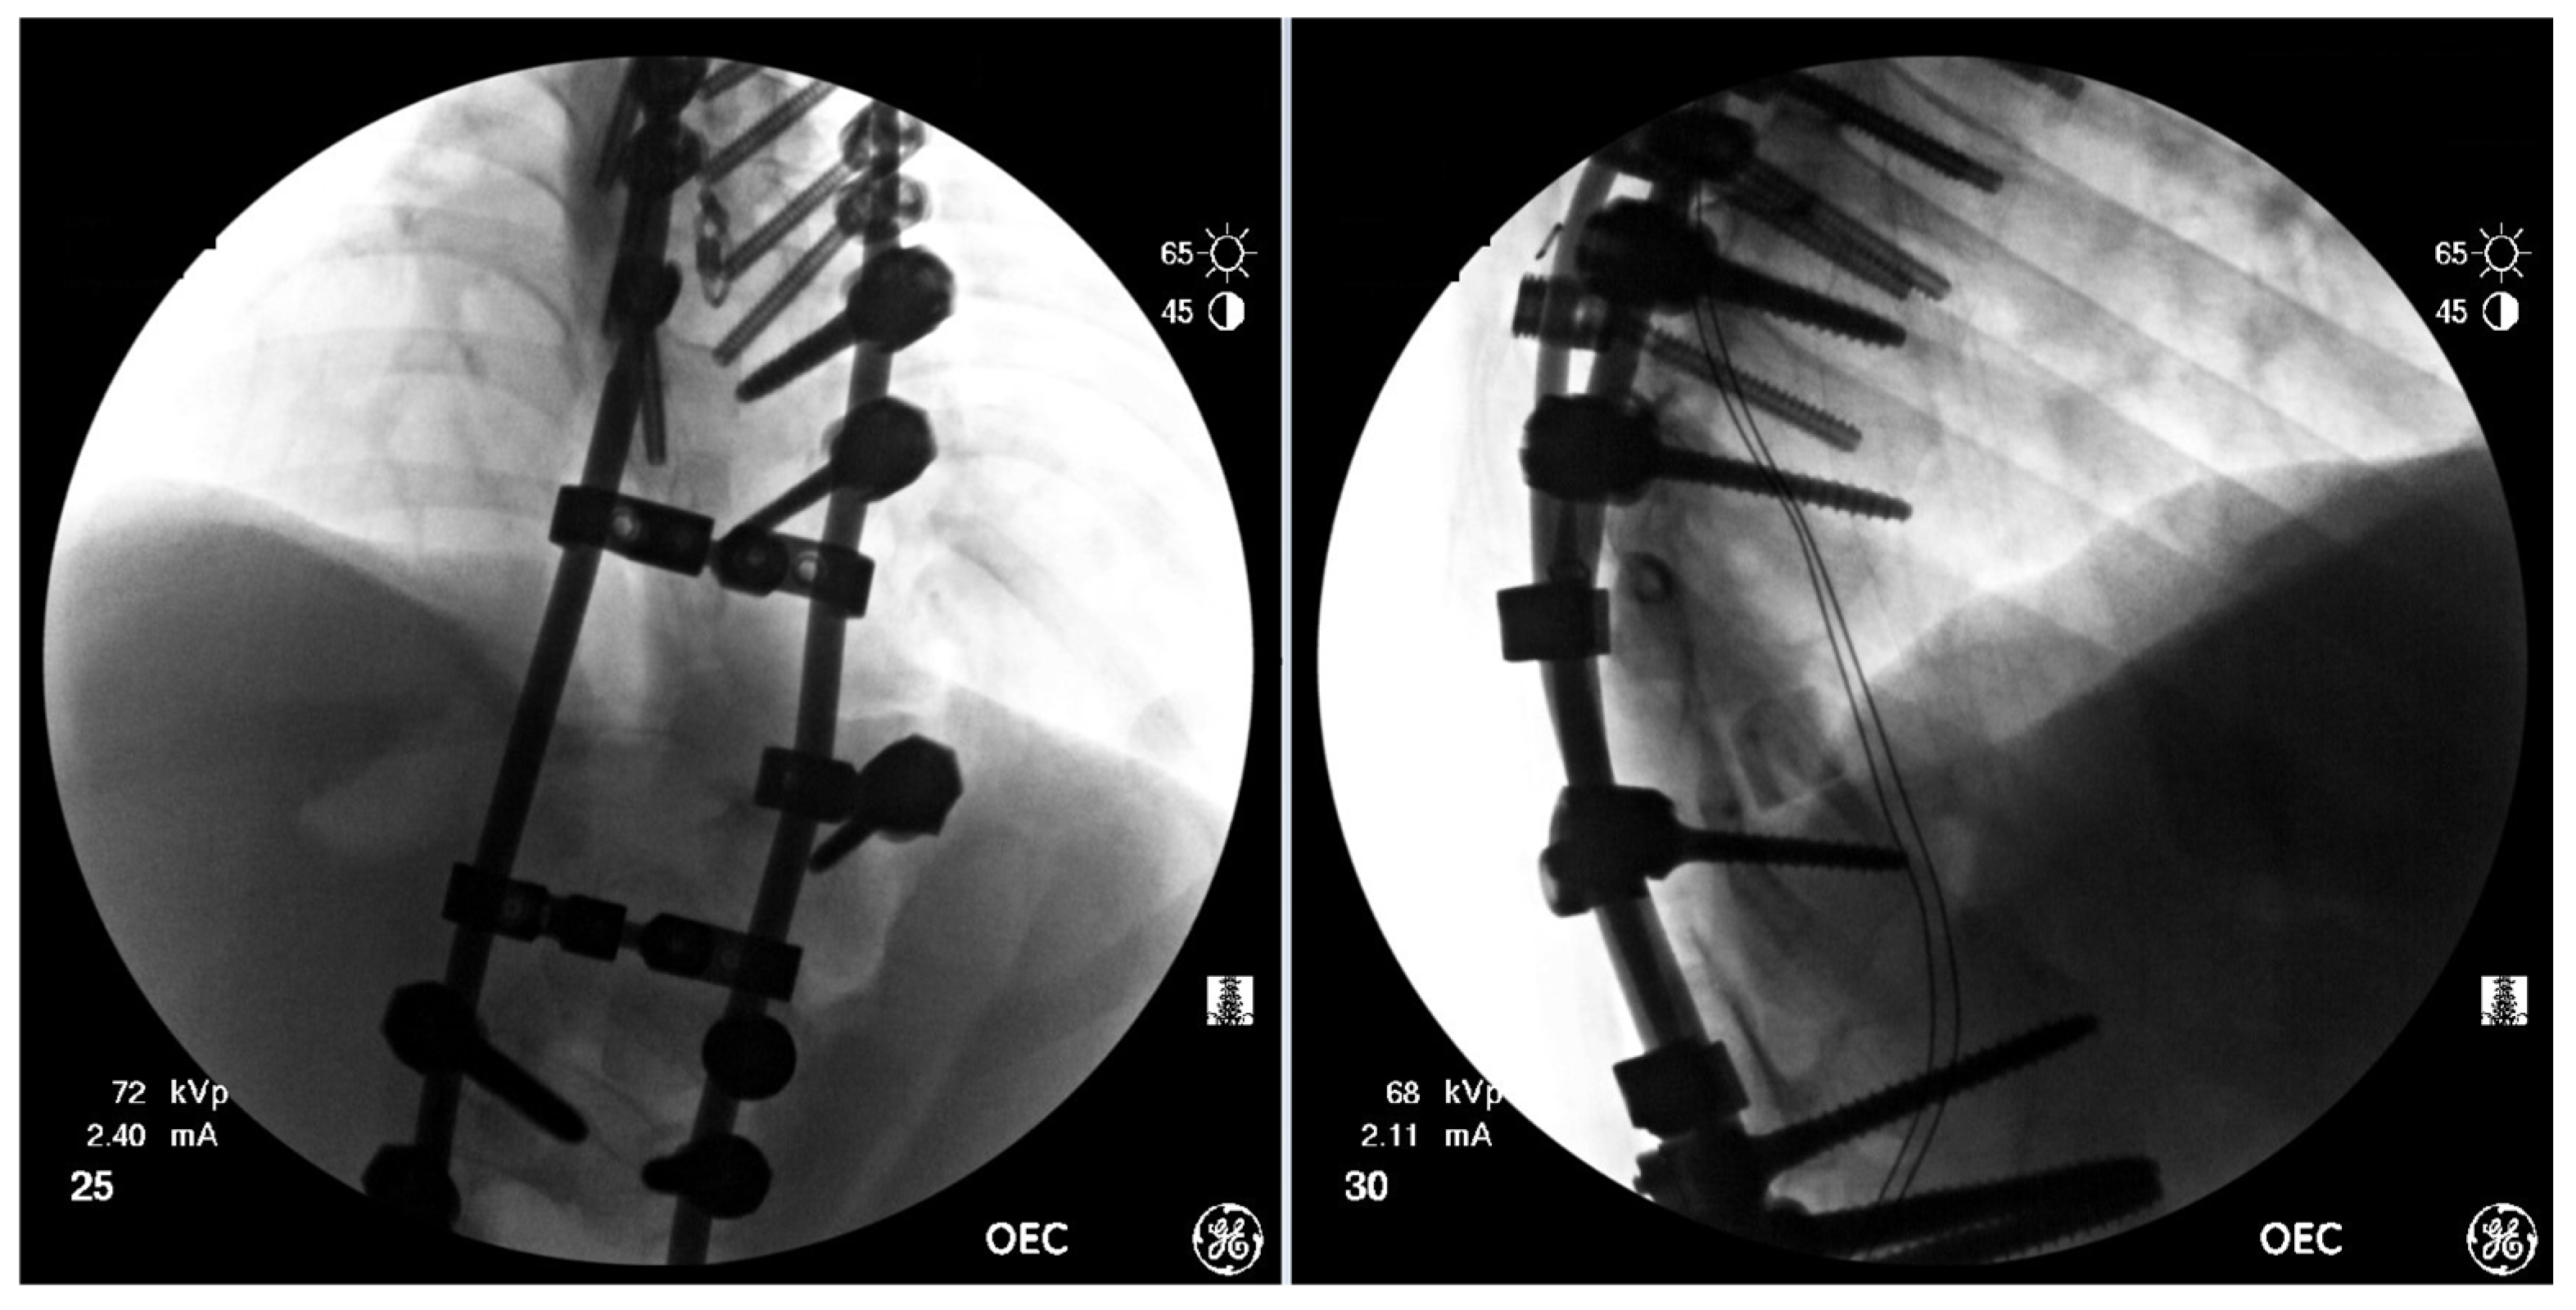

Figure 7.

AP & Lateral fluoroscopy images of temporary spinal instrumentation stabilization.